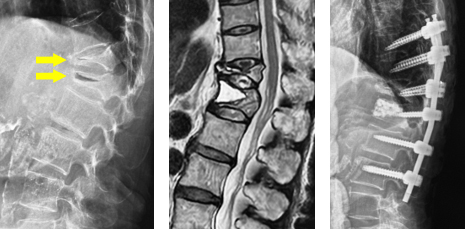

椎体形成術(VP、BKP、VBS)および後方・後側方固定術

椎体形成術でセメントや人工骨を注入して、骨折を人工的に接合します。椎体形成術のみでは固定性が弱い場合や骨脆弱性が強い場合には、スクリューなどを用いて脊椎を安定化させます。原則、手術翌日より軟性もしくは硬性のコルセットを装着し、起立・歩行を開始します。

(左)第12胸椎および第1腰椎の骨粗鬆症性椎体骨折を認めます。(中)MRIでは第1腰椎に大きな骨欠損を認め、骨折が難治性で不安定であることを示しています。(右)第1腰椎に椎体形成術を施行し、さらに骨が脆かったため、頭尾側にスクリューを挿入して固定しています。